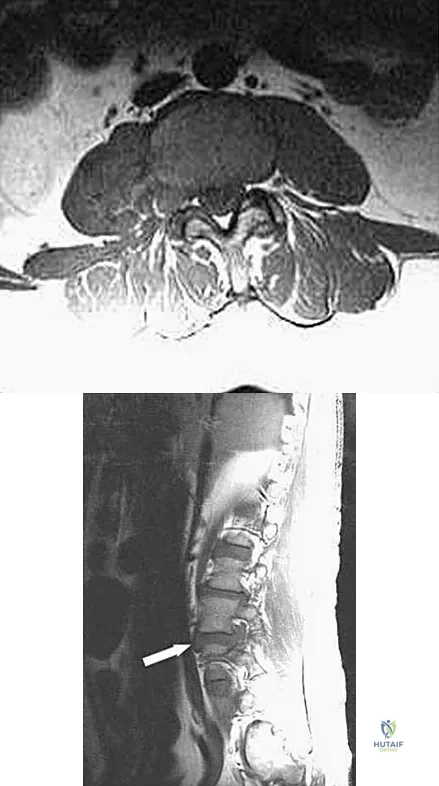

Question 32

A 32-year-old man notes increasing back pain and progressive paraparesis over the past few weeks. He is febrile, and laboratory studies show a WBC of 12,500/mm3. MRI scans are shown in Figures 6a and 6b. Management should consist of

Explanation